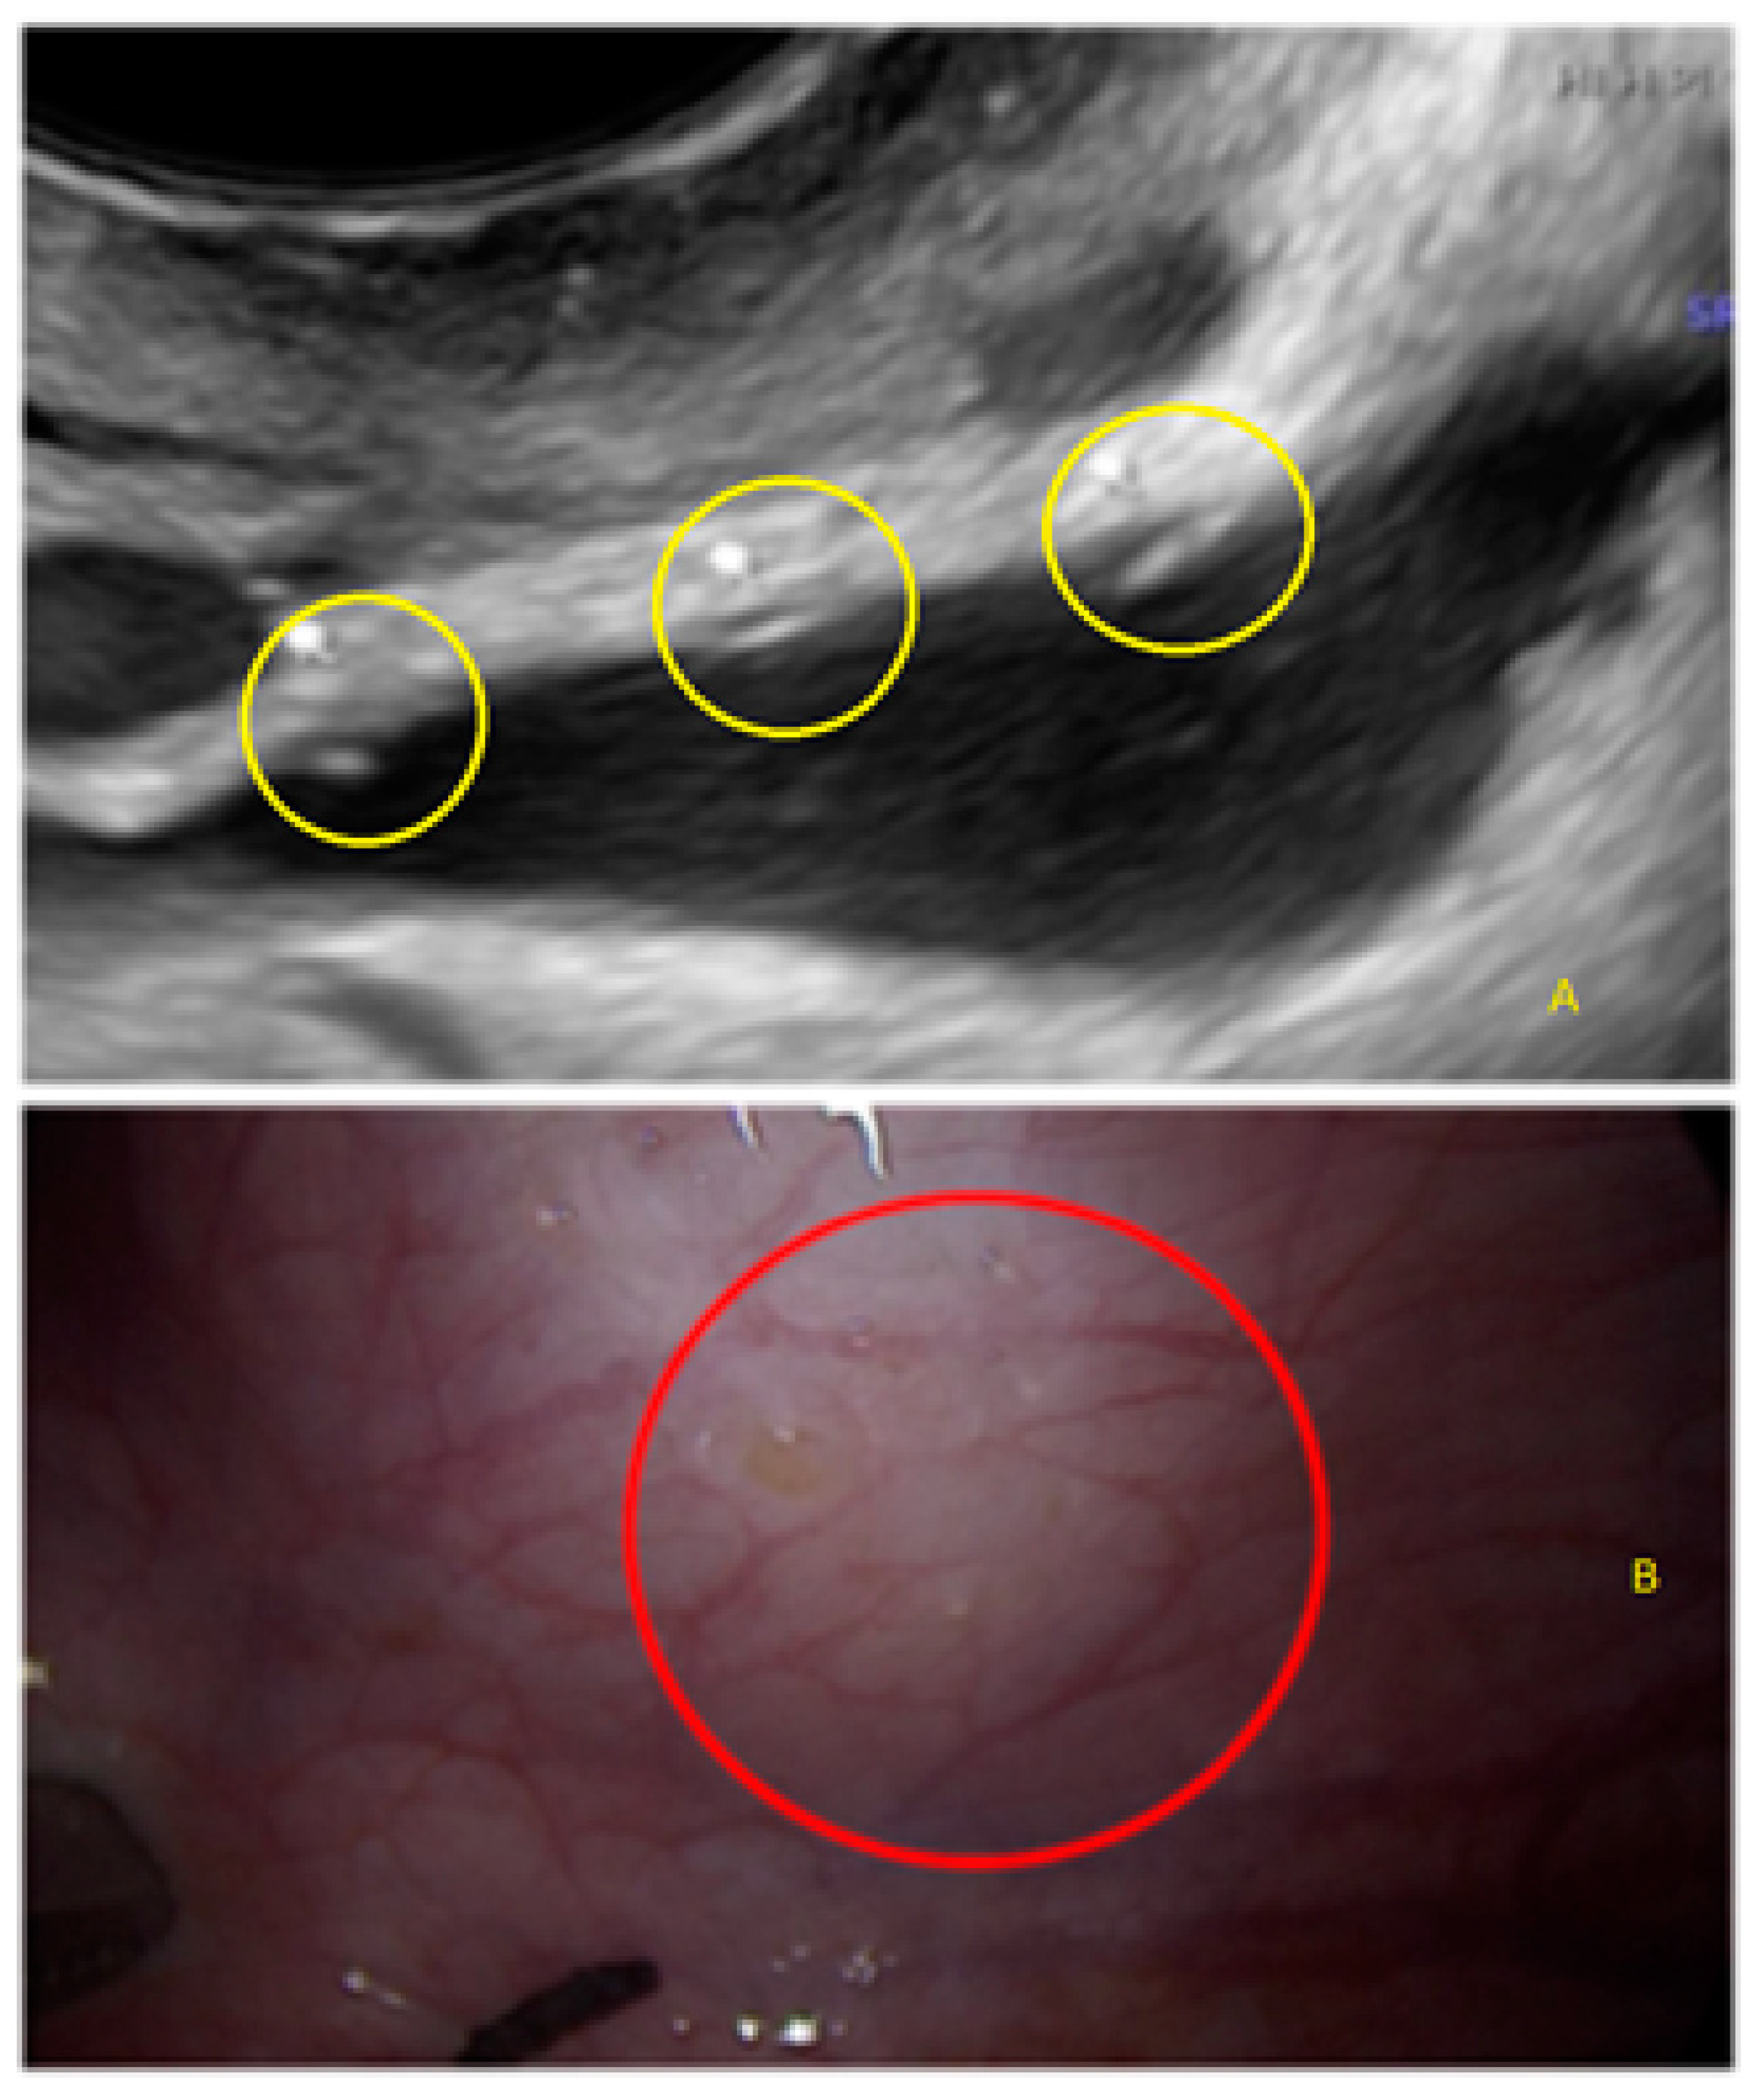

3.3. Cystic Lesions Arranged in a Cluster

4. Discussion